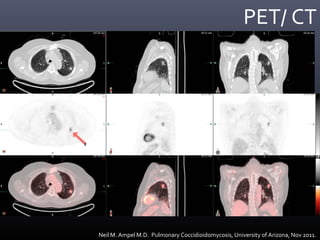

PET/ CT

Neil M. Ampel M.D. Pulmonary Coccidioidomycosis, University of Arizona, Nov 2011.